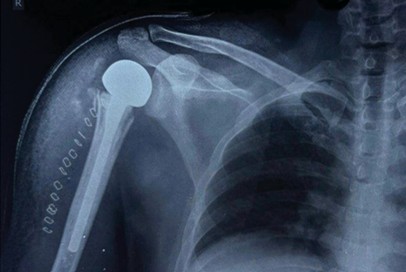

Informed consent was obtained from all participants. Demographic details and relevant medical history were collected using a structured proforma. Clinical examination and surgical intervention were carried out using standard procedures at the SBMCH. [Fig. 1] [Fig. 2] [Fig. 3] Postoperative evaluation for implant loosening was done through serial radiographs, specifically assessing for radiolucency at the bone-cement interface. Functional outcomes were assessed 26 using the CONSTANT-Murley score and UCLA shoulder score. All data were entered in Microsoft Word and analyzed using SPSS software version 24. [Fig. 4].

Figure 3: Inter-operation image.

Figure 4: Post-operative X-ray.